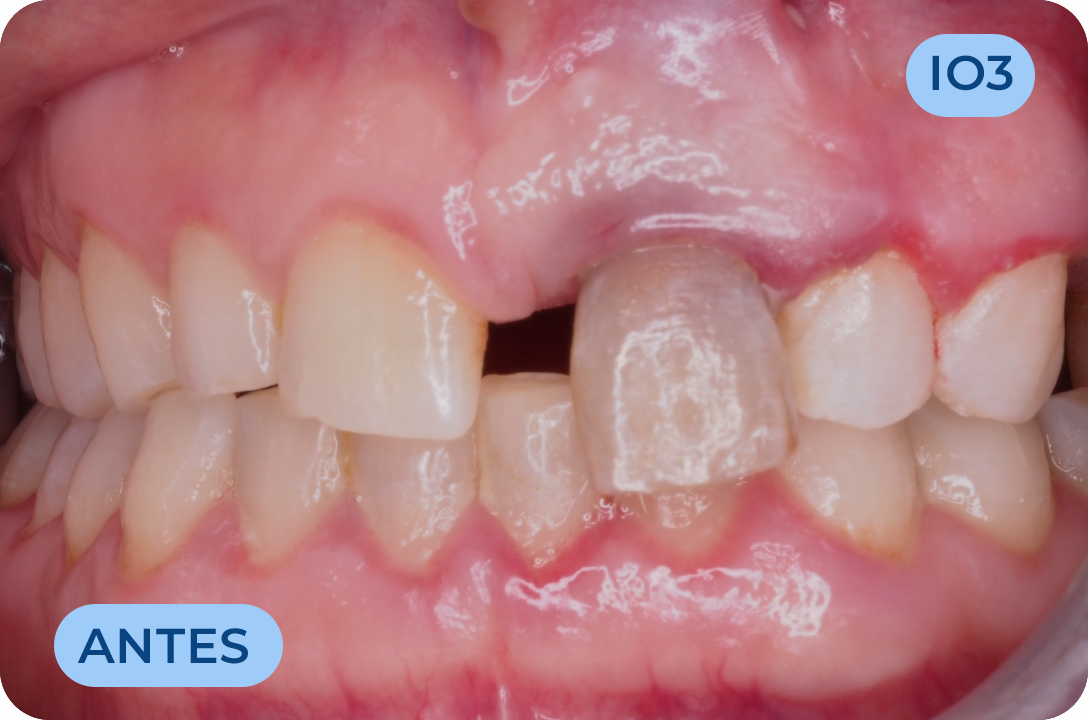

Prostodontia

É a área da Medicina Dentária que atua na substituição de dentes perdidos ou comprometidos esteticamente. Os dentes são substituídos através de dentes fixos (coroas em cerâmica suportadas por implantes ou suportadas por raízes de dentes naturais) bem como próteses removíveis. Mais recentemente surgiram as facetas (lentes de contacto) com a vantagem de conservar mais os tecidos dentários e com ótimos resultados estéticos. É uma área muito importante na reabilitação da função mastigatória assim como da auto estima, recuperando a vontade de sorrir.